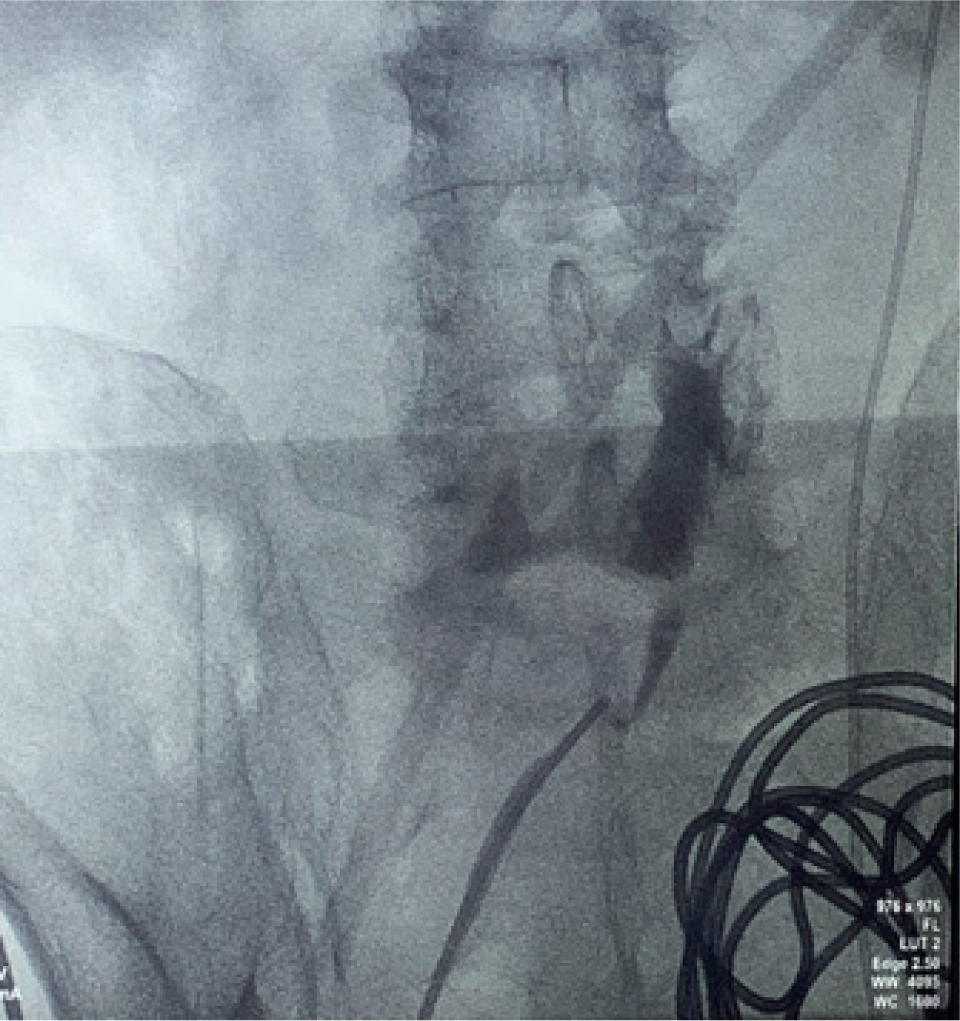

Bilateral RP and ureteric catheterization were first performed for the identification of the hila and calyces of the HSK (Figures 4 & 5). A lower midline laparotomy was performed. The tumor was identified, measuring 7 cm in diameter (Figure 6). Careful dissection of complex hilar structure was performed. Two renal arteries and two renal veins supplying the right side were identified and slung (Figure 7). The tumor was resected with artery clamping (Figure 8). The right lateral calyx of the pelvicalyceal (PC) system was involved and resected. The PC system was closed with 3/O PDS. Renorrhaphy was completed with 3/O V-Loc, and parenchyma was closed with 2/O V-Loc. Ischemic time was 20 minutes, and total operation time was 332 minutes. Blood loss was 420 mL. The patient had completed 1 week of levofloxacin and was discharged on postoperative day 6 with one kick of fever that spontaneously subsided.

Figure 4: Left renal pelvis.

Figure 5: Right renal pelvis.